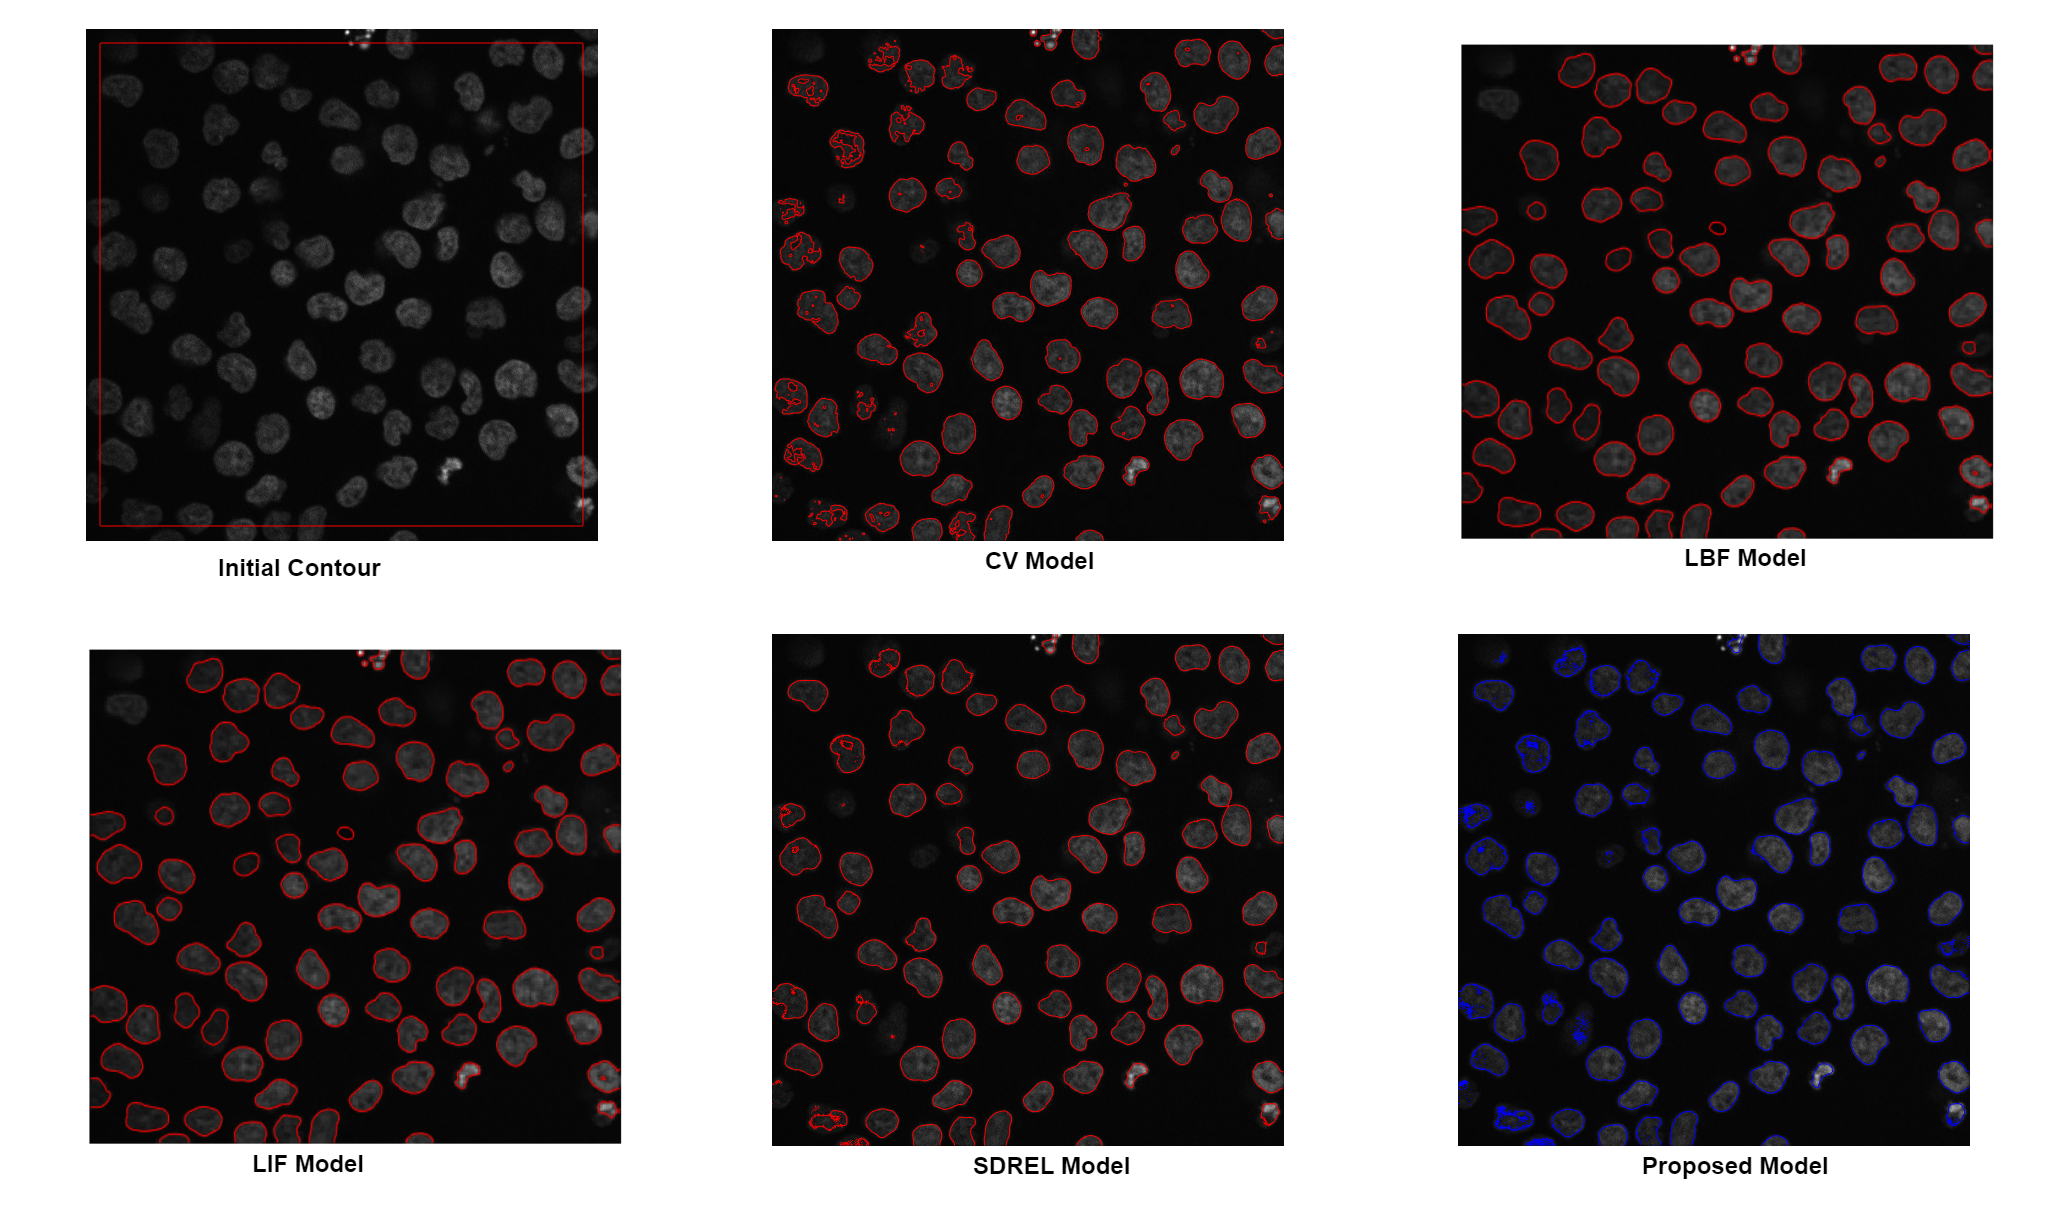

This section describes the efficiency of the proposed model on some real-world images. For instance, consider a microscopic image of cells in grayscale, as shown in Fig. (9), from which we want to extract all the cells from the background using image segmentation tools. Furthermore, the cells have weak boundaries and a highly related intensity as the background. Therefore, it is difficult to extract these cells from a black background using an ordinary model. Here, we need a model capable of extracting all the microscopic cells from a dark background. The experiment results show that, while using a global region-based model for cell detection, such as the CV model, the segmentation is poor, whereas a local region based model such as an LBF or an LIF extract the cells more precisely. However, they also miss some cells that have almost the same intensity as the background. Although the SDREL model uses global image information, owing to its edge-based term it also segments many cells from the background. By contrast, results of the proposed model indicate that it segments almost all the microscope cells from the black background with more accuracy and speed.